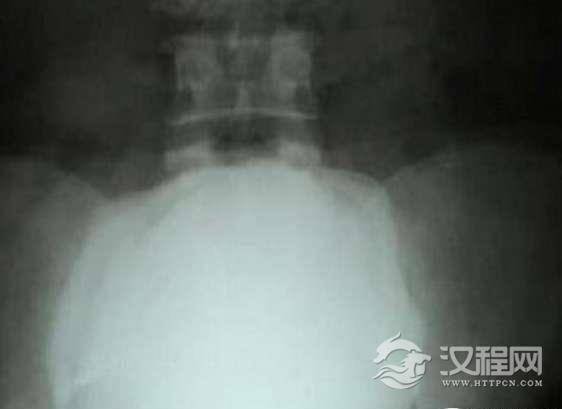

在印度,有一位男子叫帕特尔,今年50岁。近日在医生的帮助下,成功取出体内一颗直径达10厘米的大结石,结石重达2.8斤,一举打破7年前,同样是一位印度男子创下的记录,那位男子患有癌症,体内出现了一个2.4斤的结石。

这件事来的很突然,有一天晚上,帕特尔的肚子就突然疼起来了,犹如阑尾炎一般,但当他去到医院后,经过医生的检查,才知道了这块结石的存在。手术历经一个多小时,由于医生事先已经给帕特尔拍了X光,所以手术非常的顺利。